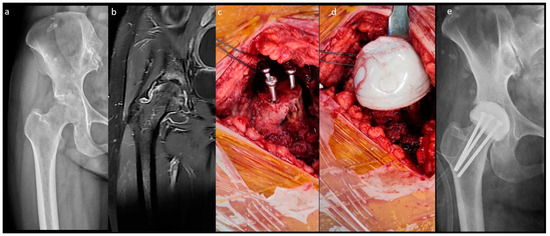

Figure 1.

Non-medullary-sparing (n-MS) spacers. (A) Pre-operative radiograph showing cartilage destruction with the subchondral collapse of the femoral head, (B) pre-operative MRI showing diffuse fluid accumulation within the joint, (C) fabrication of the n-MS spacer using a silicone mold, (D) the hip joint with the n-MS spacer implanted, and (E) post-operative radiograph with the n-MS spacer in situ.

The n-MS spacer (Figure 1) was fabricated with an intraoperative silicone mold. Four sizes of the spacer trials and molds were available (Supplementary Table S1). After dislocation, the femoral neck was osteotomized with one finger width left above the lesser trochanter. The size of the femoral head was measured, and then a roughly compatible spacer size was determined. The acetabulum was prepared with a reamer to remove residual cartilage until oozing and 1 mm greater than the selected spacer head size. Then, the femoral medulla was prepared with a broach to fit the corresponding size of the spacer stem. Molding of the spacer and bony preparation were performed simultaneously. The spacer was prepared with a curved 3.0 mm Kirschner wire or 10.0 mm stainless-steel rod as the central endoskeleton until the cement cured. After adequate debridement, the spacer was cemented proximally within the medulla with a neutral version [17]. The hip was reduced, stability was assessed, and the capsule was repaired.